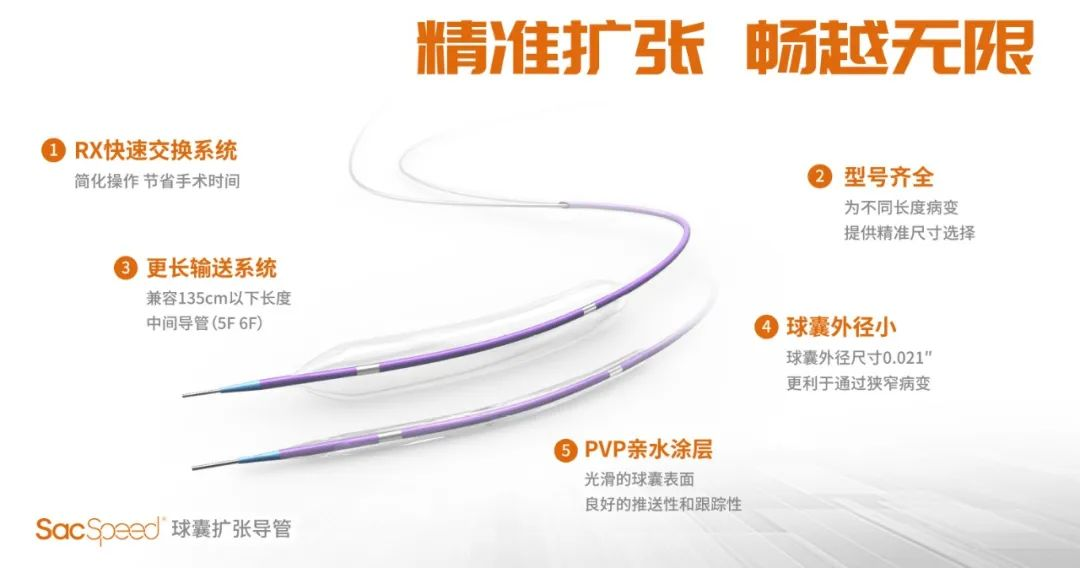

国产加奇SacSpeed®2.0mm×15mm球囊试用体会

快速交换系统简化操作流程,省时省力

相较于Gateway外径尺寸小,易于通过病变部位

球囊顺应性好,到位能力强

150cm工作长度,如需使用中间导管不担忧出不了头

尺寸规格齐全,可选择范围大